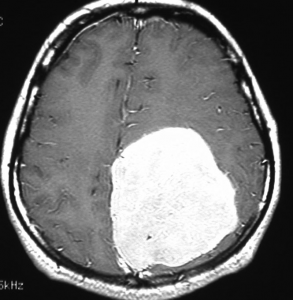

手術後のMRIです。腫瘍は全部取れていて後遺症もありません。圧迫されて変形していた脳はきれいに元に戻っていますし脳浮腫も消えました。一般的に若い人の脳ほどきれいに元に戻ります。注意しなければならないのは,少しでも取り残した場合には,何年か後に10%-20%くらいで再発があることです。もちろん完全に取れた時の再発はほとんどありません。